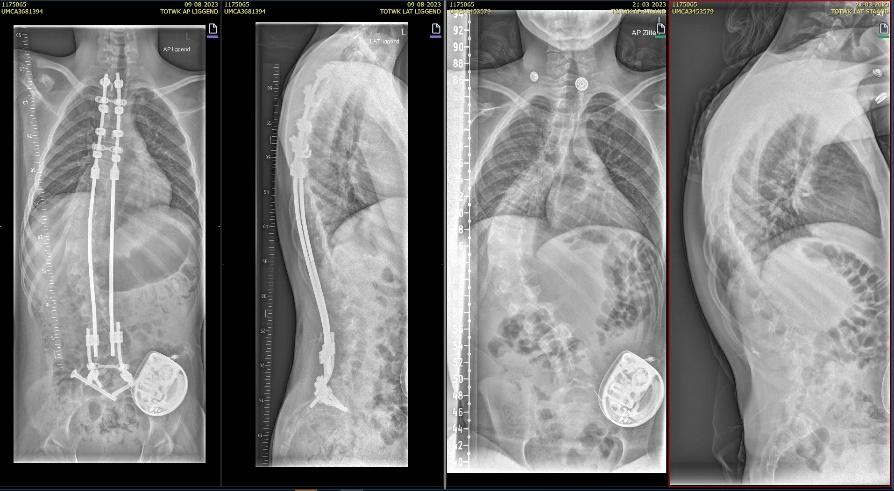

De precieze ingreep, met name hoeveel wervels er worden vastgezet, bepaalt de orthopedisch chirurg aan de hand van rontgenfoto’s.

Als de voorbereidingen klaar zijn begint de operatie. De orthopedisch chirurg hangt kleine gewichtjes aan je benen en hoofd zodat je goed recht ligt. Hiervoor plaatsen we een klem net boven je oren, na de operatie is deze weer verwijderd maar heb je twee kleine gaatjes.. De orthopedisch chirurg maakt een of twee wond(en) op de rug. Tijdens de operatie maakt de chirurg de bocht in jouw wervelkolom zo recht mogelijk. De wervelkolom wordt vastgezet met behulp van titanium staven (of kobalt chroom) en schroeven of haakjes.

Bij neuromusculaire scolioses wordt er over het algemeen gekozen voor een “bipolair systeem”

Bij deze operatie zetten we de wervelkolom vast door middel van 2 verankeringspunten aan de ruggenwervels, boven tussen de schouderbladen en onder in het bekken. Hiervoor maken we een wond tussen de schouderbladen, onderin bij de lage rug, en ter hoogte van het bekken 2 kleine wondjes. De twee verankeringspunten verbinden we met elkaar door een metalen staaf onder de huid te schuiven. Met de staven kunnen we de rug rechter maken.

Rontgen foto voor (links) en na (rechts) scoliose correctie

Controle röntgenfoto

Vlak voor je naar huis gaat maken we ter controle een röntgenfoto van je wervelkolom om te controleren of de ankerpunten goed zijn geplaatst en hoe de correctie van de scoliose eruit ziet.